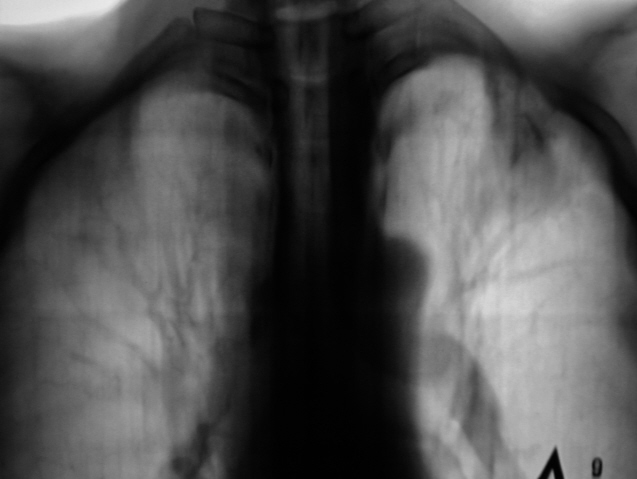

На обзорной рентгенограмме органов грудной полости, произведенной в прямой стандартной проекции, слева на уровне 1 межреберья определяется снижение прозрачности легочной ткани в виде инфильтративной (фокусной тени), округлой формы. Данная фокусная тень соединяется с корнем левого лёгкого при помощи "дорожки".

При анализе "тени фокусной тени". Тень средней интенсивности, неоднородной структуры (с несколькими, различных размеров и формы просветлениями), с нечеткими контурами.

Рентгенологически выставлен диагноз инфильтративного туберкулеза верхней доли левого лёгкого, с преимущественным поражением 1 сегмента в фазе распада. Пациент госпитализирован с туб. отделение, выявлены МБТ.

Хочу уточнить. Это не боковой прицельный снимок, это фрагмент "боковой рентгенограммы", только с большим увеличением и распад, как Вы совершенно правильно заметили, просматривается на фоне инфильтрата.